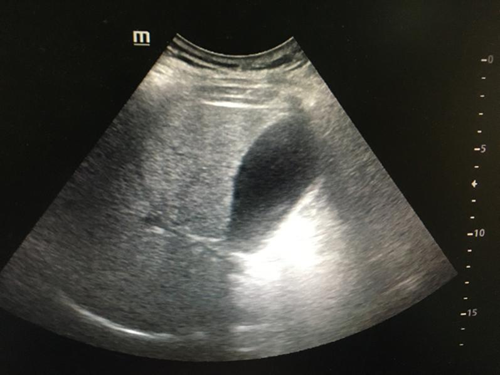

(1)轻、中度脂肪肝:肝大小正常,实质回声均匀、细密、轻度增强,轻度脂肪肝的肝内管道结构清晰,中度脂肪肝的肝内管道结构稍模糊,但仍可辨认清楚,后方回声轻度衰减,深面膈肌可显示。

(2)重度脂肪肝:肝脏体积增大,形态饱满,肝回声均匀、细密、明显增强,肝内管道结构模糊不清,后方回声明显衰减,深面的膈肌显示不清。